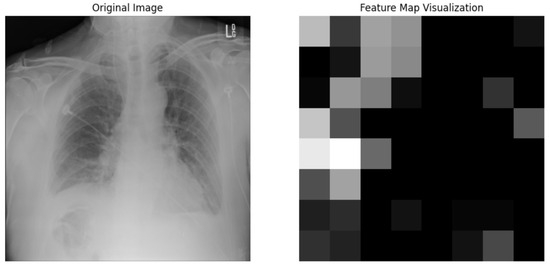

5.4.1. Local Interpretable Model-Agnostic Explanations for Clinical Validation

We applied scientific analysis on a random 7 sample, which was provided by the clinical specialist. The LIME Analysis for Image Data (a), (b), (c), (d), (e), and (f) is in Figure 22, Figure 23, Figure 24, Figure 25, Figure 26 and Figure 27. There are two parts of LIME analysis from the provided chest X-ray images to detect the disease area. Original Image and LIME explanation;

• Original Image: The patient’s thoracic cavity. It displays the typical anatomical structures of the chest, including the lungs, ribs, and heart.

• LIME Explanation: The result of applying LIME to the chest X-ray image. The yellow boundaries indicate the regions of the image that were most influential in the model’s decision-making process when determining whether the image indicated a particular condition. In this context, these regions are the parts of the X-ray that the AI model considered most important for making its diagnostic prediction.

The analysis very useful for clinicians to understand the model’s behavior and ensure that it aligns with medical expertise. The use of LIME helps in making the AI model’s interpretability decisions more transparent and interpretable. It allows medical professionals to verify whether the AI’s focus areas correspond to clinically significant regions. It also enhanced diagnostic capability of understanding which parts of the images in the AI model in refining the model further and ensures that it makes accurate and reliable predictions. This is particularly crucial in medical diagnostics where interpretability and accuracy are paramount.

Figure 23. LIME Analysis for Image Data (b) on original image to LIME explanation.